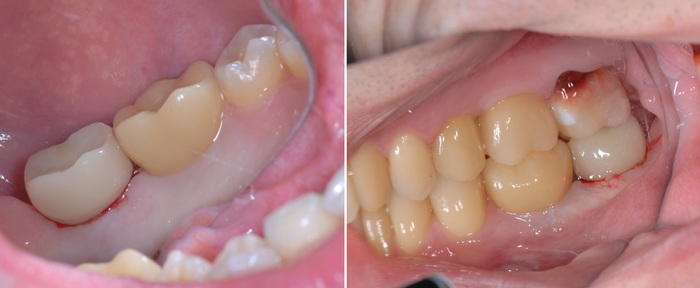

Было принято решение начать с правой стороны:

Произведена установка 3 имплантатов и синус-лифтинг в области 5-го и 6-го зуба на верхней челюсти и 6-го на нижней. В полости рта это выглядело примерно так:

Спустя примерно 3 месяца пришла очередь левой стороны:

Также были установлены 2 имплантата и проведен синус-лифтинг на верхней челюсти (в области 5-го и 6-го зуба) и 1 на нижней (в области 6-го зуба).

После установки имплантатов достаточно 3.5 месяцев до снятия слепков и изготовления временных коронок. Изготовление коронок проходило так же в два этапа по сторонам. Я не вижу смысла добавлять много + - одинаковых картинок, поэтому вот результат с временными коронками сразу на всех установленных ранее имплантатах.

В полости рта это выглядит так:

Я решил добавить фотографии сразу после снятия брекетов, а не с ними, как это было на рентгеновском снимке. Думаю, так выглядит намного симпатичнее.

Коронки страшненькие – на то они и временные. Такой тип коронок необходим для «доформирования контура десны» и для того, чтобы «ввести области в жевание» из-за длительного отсутствия зубов. Необходимо подготовить мышцы, связки, сустав, остальные зубы к нормальному жеванию. Временные коронки можно корректировать при необходимости.